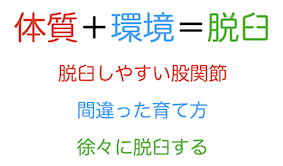

どうして脱臼するの?

脱臼しやすい股関節で生まれてきた児が、間違った方法で育てられることによって、徐々に脱臼が進行します。出生時に脱臼していることは少ないので、最近は「先天性股関節脱臼」ではなく「発育性股関節形成不全」と呼ばれています。